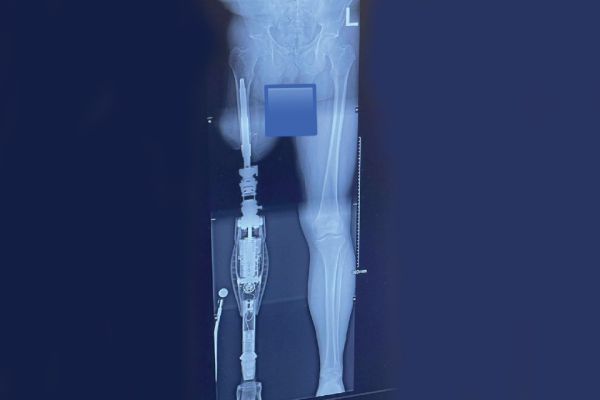

With an amputee-centered approach, Quebec-based Ethnocare has innovated a prosthetic solution to manage residual limb volume fluctuation for better comfort, stability and limb health for lower extremity amputees.